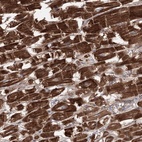

Immunohistochemical staining of human heart muscle shows strong cytoplasmic positivity in myocytes.